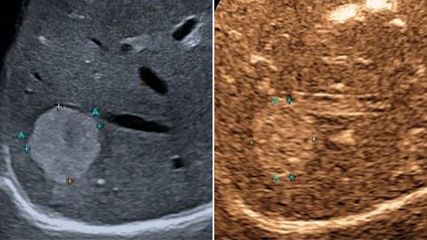

Die Arbeitsdiagnose einer MASLD (mit metabolischer Dysfunktion assoziierte steatotische Lebererkrankung – bis vor Kurzem als NAFLD bezeichnet) ist einfach: Wird mittels Bildgebung, in der Regel Ultraschall oder Biopsie, eine Steatose der Leber festgestellt und liegen kardiometabolische Risikofaktoren, jedoch kein hoher Alkoholkonsum vor, so kann von einer MASLD ausgegangen werden. Kommen Inflammation und möglicherweise Fibrose hinzu, so spricht man von MASH (mit metabolischer Dysfunktion assoziierte Steatohepatitis). Bei 80% der Betroffenen bleibt es bei einer Steatose mit allenfalls minimalem Progressionsrisiko, erläuterte Univ.-Prof. Dr. Herbert Tilg, Leiter der Innsbrucker Universitätsklinik für Innere Medizin I. In 20% der Fälle liegt jedoch eine MASH vor, die mit einem beträchtlichen Risiko für Progression zu Zirrhose und Dekompensation sowie mit einer erhöhten Inzidenz von Leberkarzinomen assoziiert ist. In dieser Patientengruppe ist die Mortalität signifikant erhöht, wobei kardiovaskuläre Todesursachen die größte Rolle spielen. Daher besteht erheblicher Bedarf an wirksamen Therapien, so Tilg, der ergänzte, dass man bis heute nicht vollständig verstehe, warum es bei der Mehrheit der Betroffenen bei MASLD bleibt, während ein Teil eine MASH entwickelt. Dabei dürften extrahepatische Signale, unter anderem aus dem Fettgewebe, aber auch bakterielle Stoffwechselprodukte aus dem Darmmikrobiom eine wichtige Rolle spielen.1